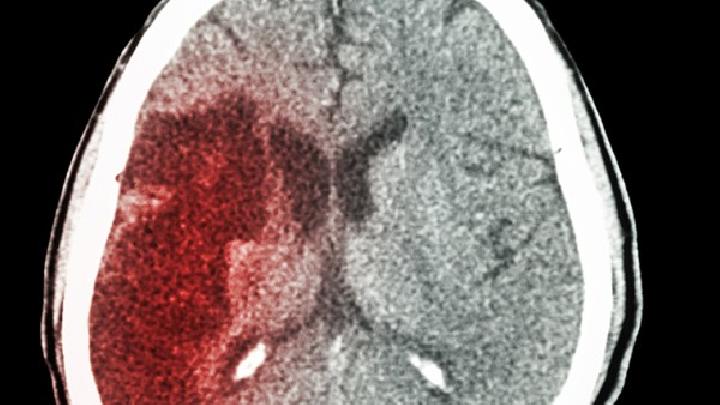

6.脑血管疾病:"脑萎缩,痴呆"最常见的原因。主要有脑梗死、脑血栓形成、脑出血等疾病,由于血液粘度增加、血流缓慢、血管壁粗糙等一系列因素,导致壁血栓形成、血管腔狭窄甚至堵塞,导致脑组织细胞缺血、缺氧、萎缩甚至坏死,最终形成脑萎缩、痴呆直至死亡。